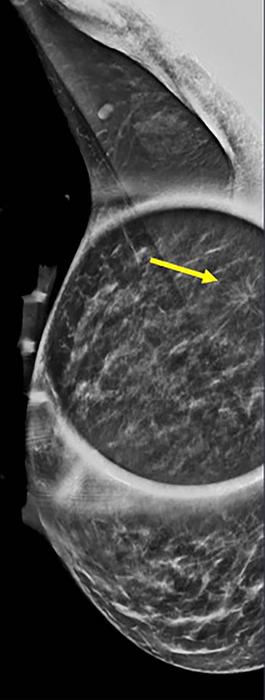

Mammogram shows spot on right mediolateral oblique (side angle) view. (IMAGE)

Spot on right mediolateral oblique (side angle) view. Area of distortion persists on additional mammographic views, and a mass is identified on subsequent breast ultrasound. Ultrasound guided biopsy was performed and revealed nuclear grade 1 invasive ductal carcinoma.